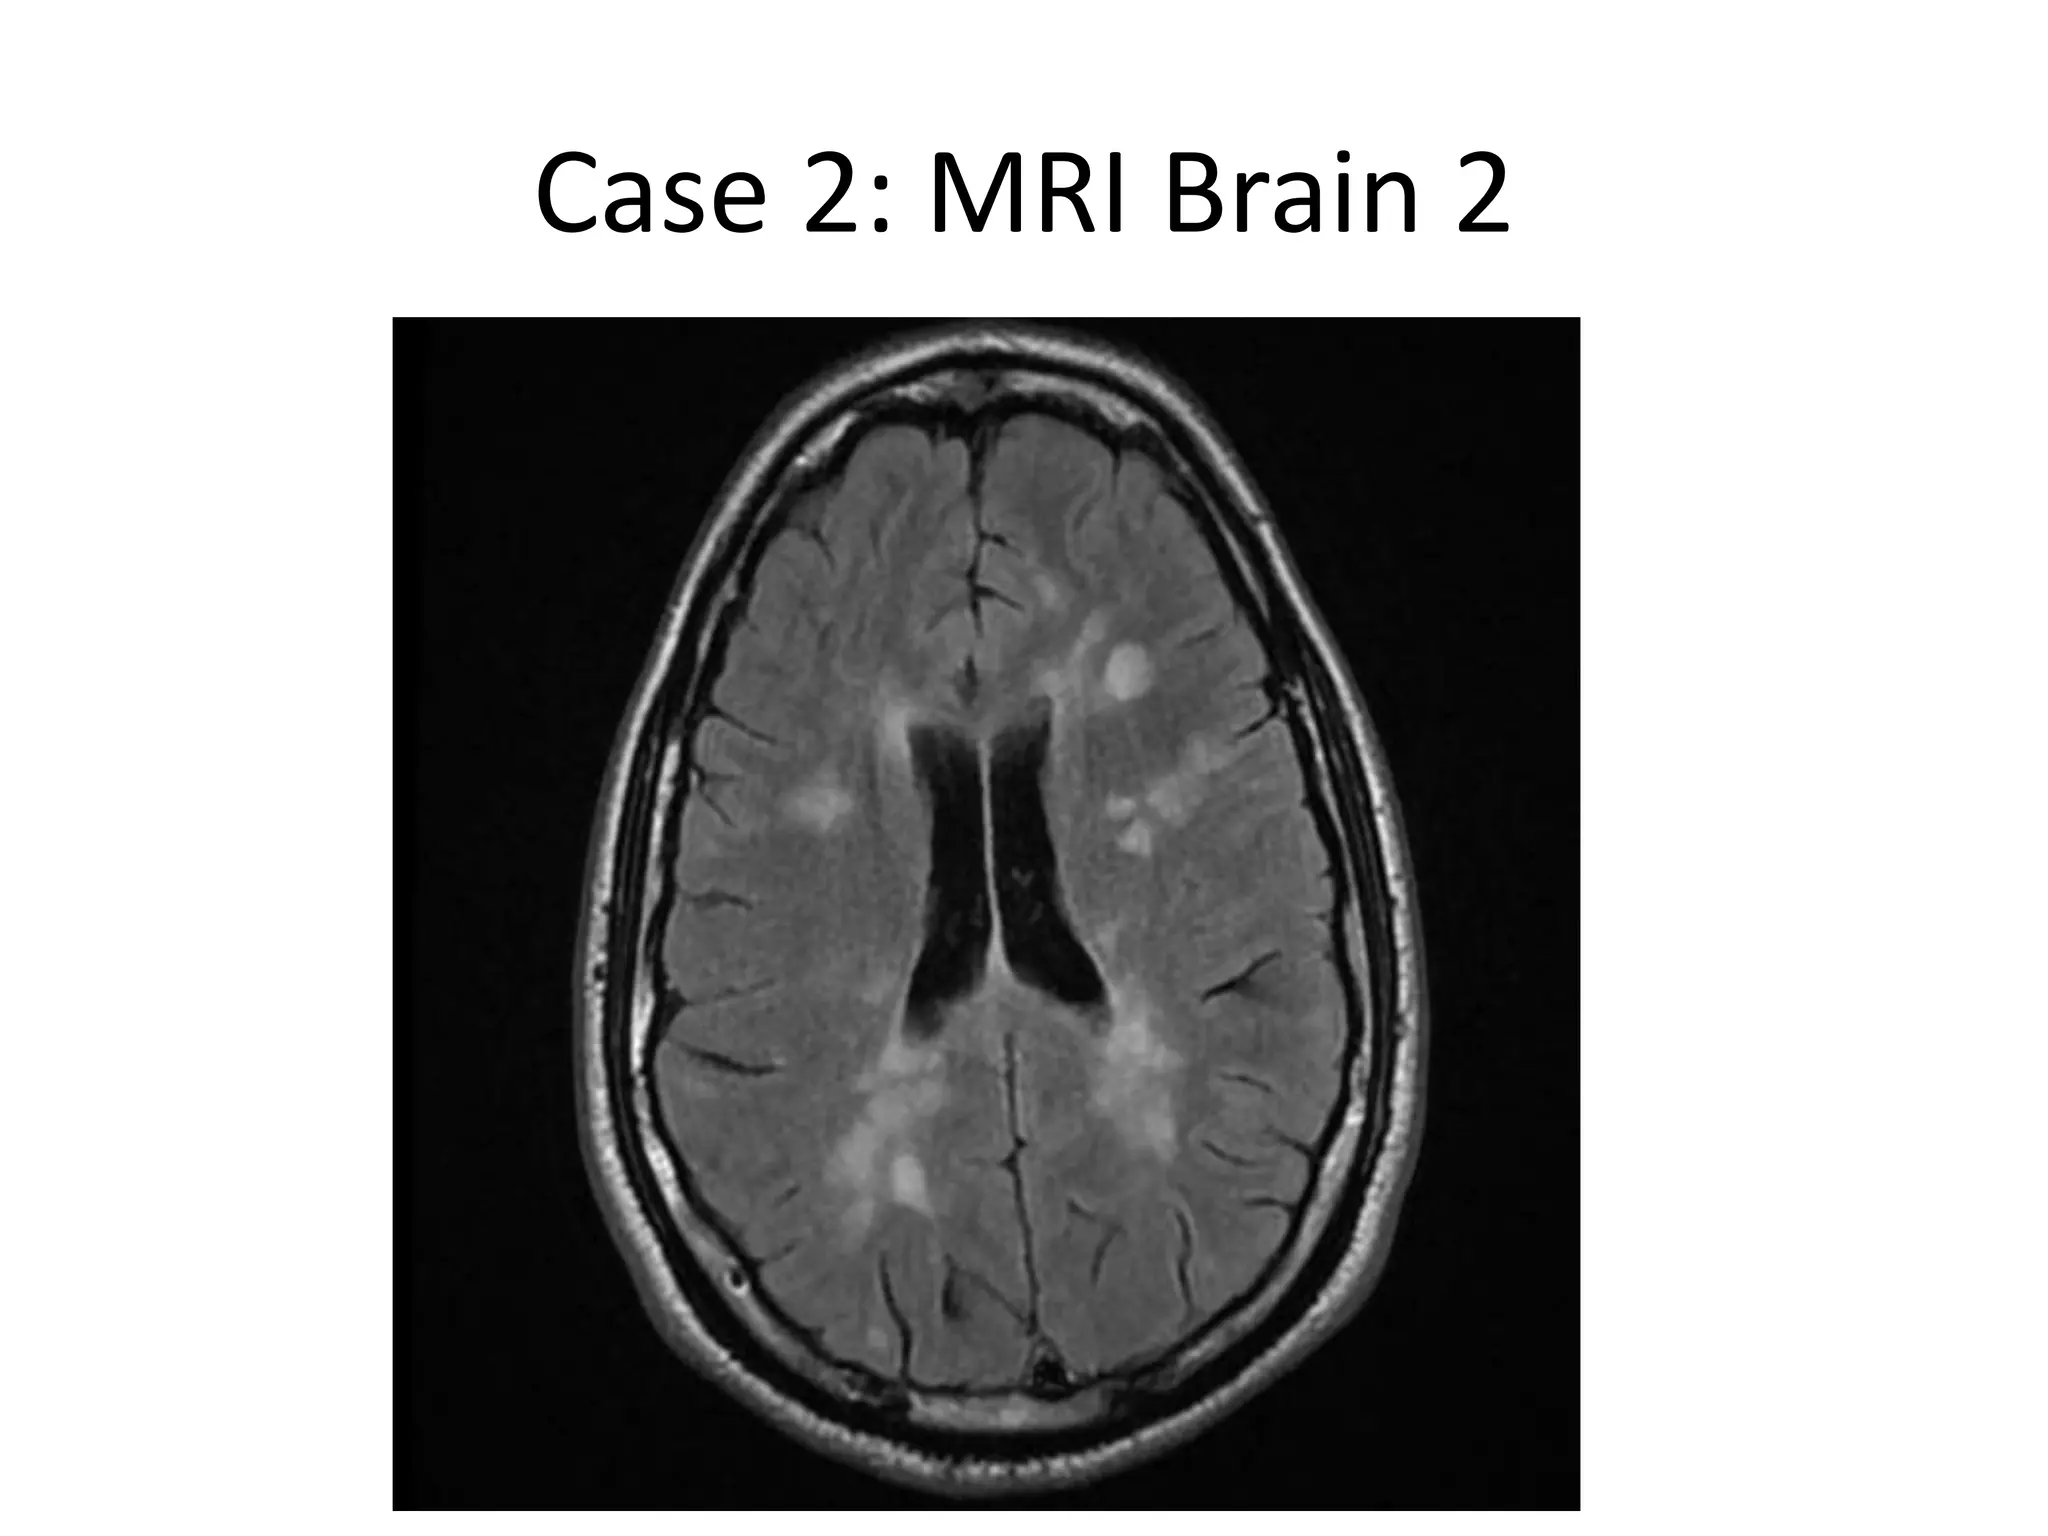

Case 2: MRI Brain 2

Case 2 • InSept 2013, patient came with another severe relapse , with homonymous hemianopia, sphincteric problems, gait ataxia, and sensory disturbance. • Treated with pulse steroids with partial improvement in urinary symptoms and ataxia, but not in visual symptoms.

Case 2: MRIBrain 2

Case 2 • MRIshowed marked worsening, with tumefactive enhancing lesions • A CSF study was done, which was normal, negative for JCV. • Considering this as a failure of Tysabri, it is planned to treat him with Rituximab